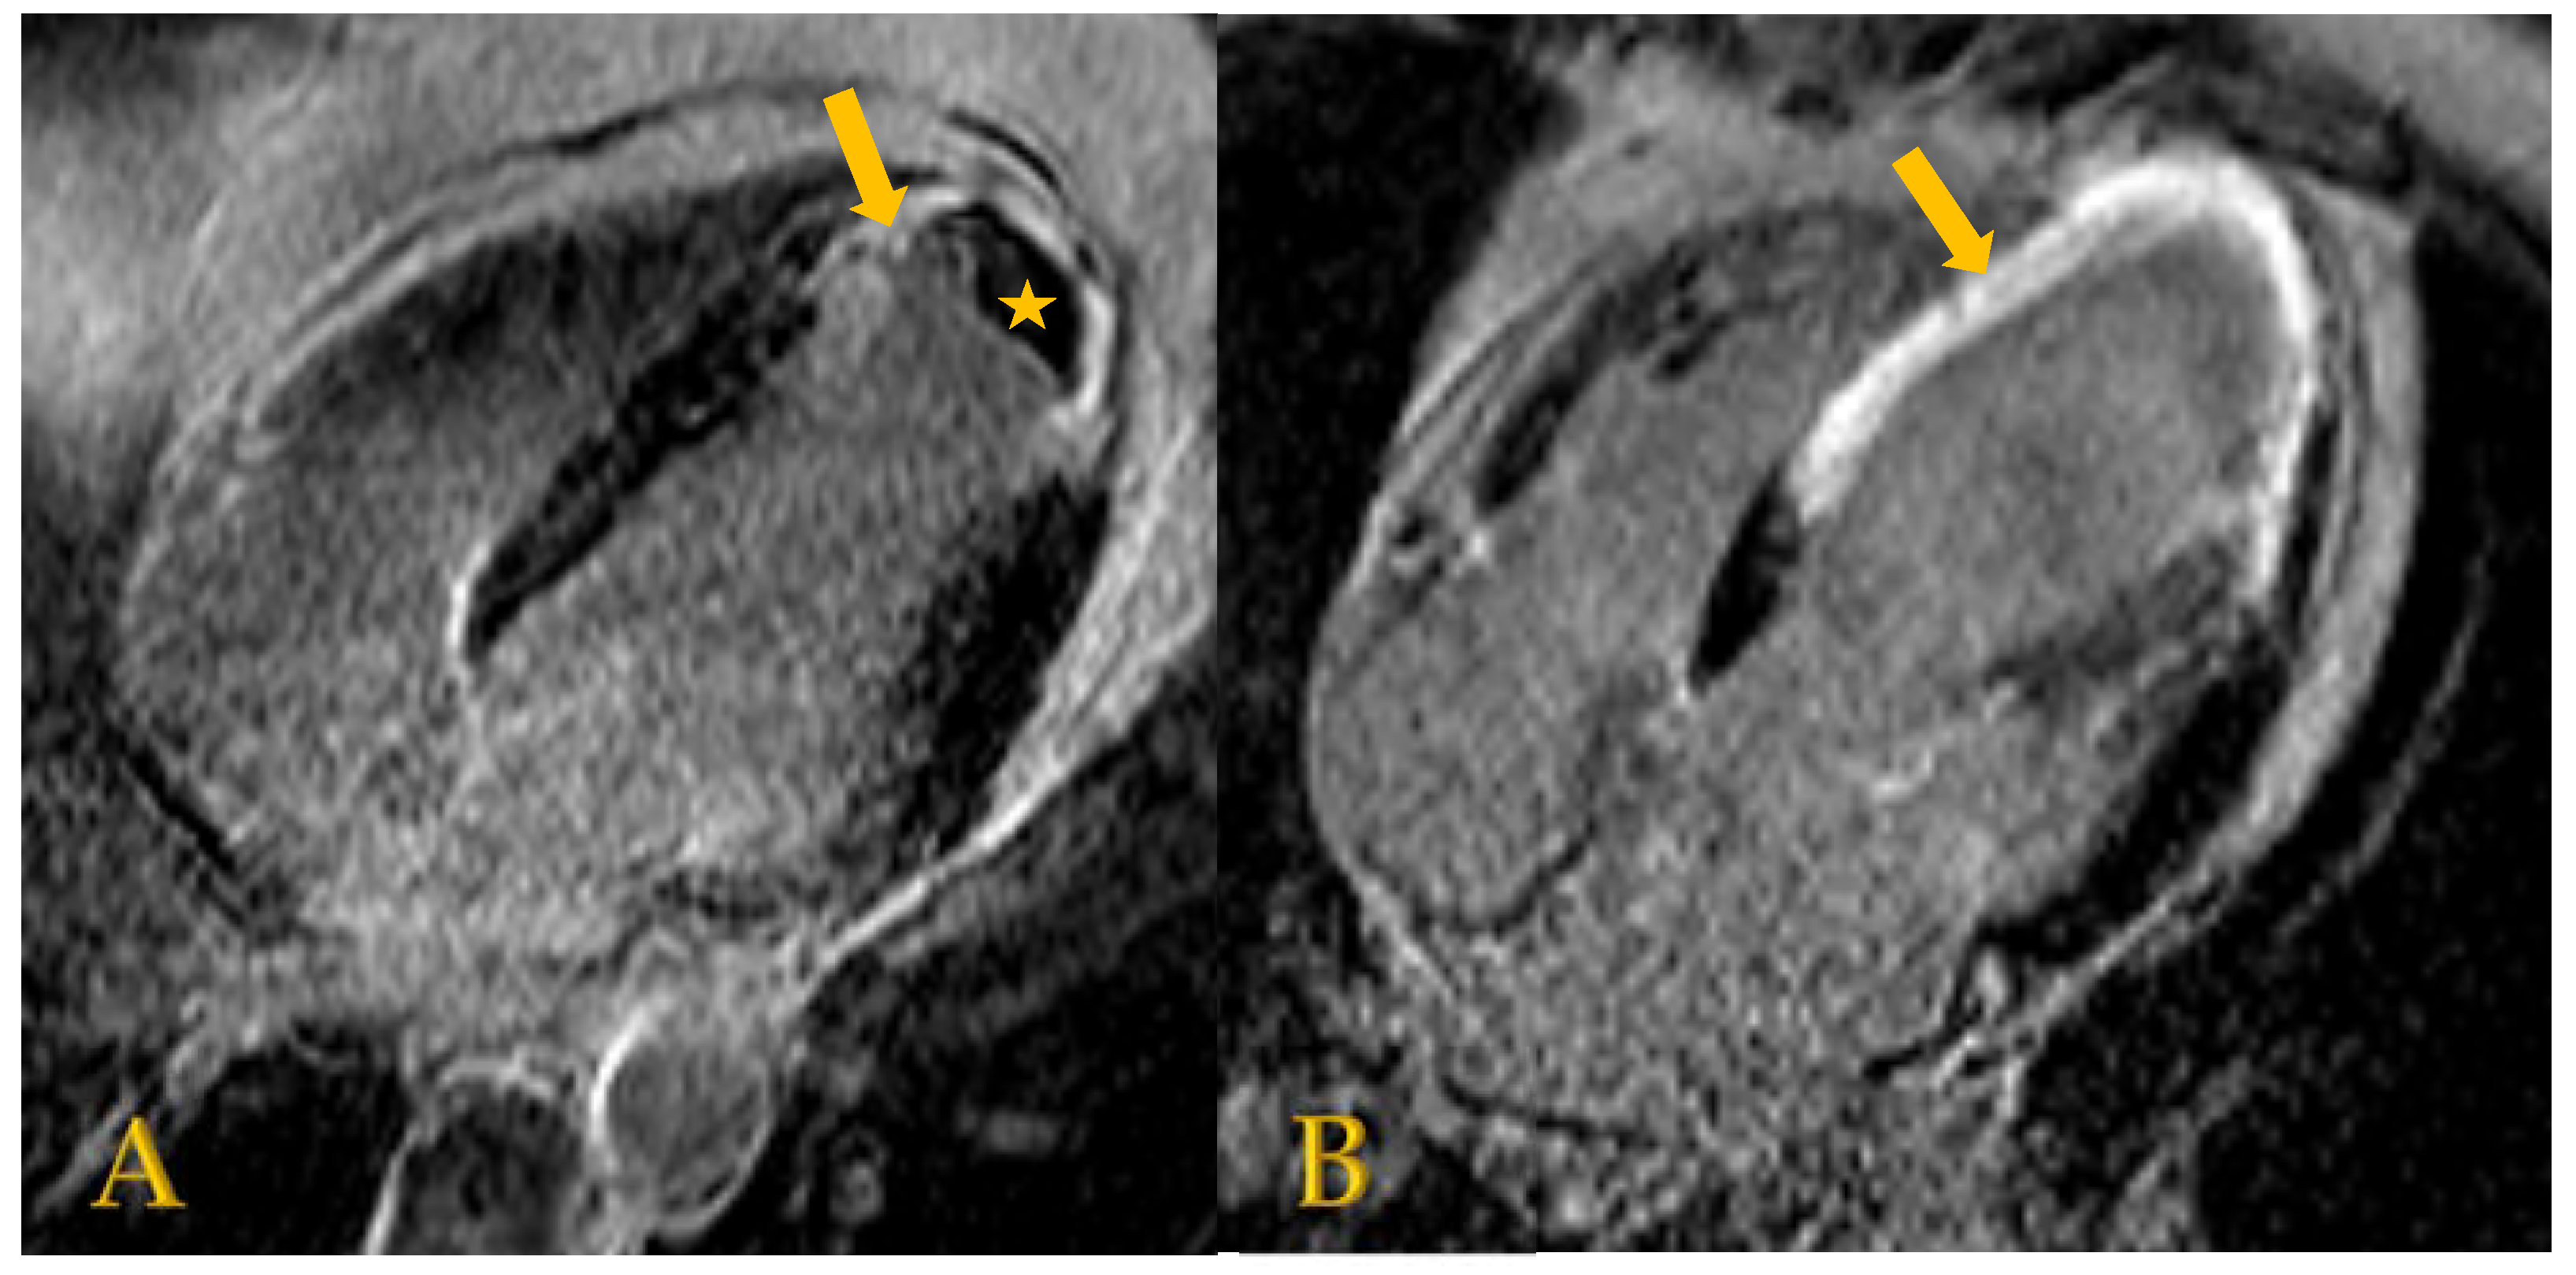

5.2. Cardiac Magnetic Resonance (CMR) Imaging with Late Gadolinium Enhancement (LGE)